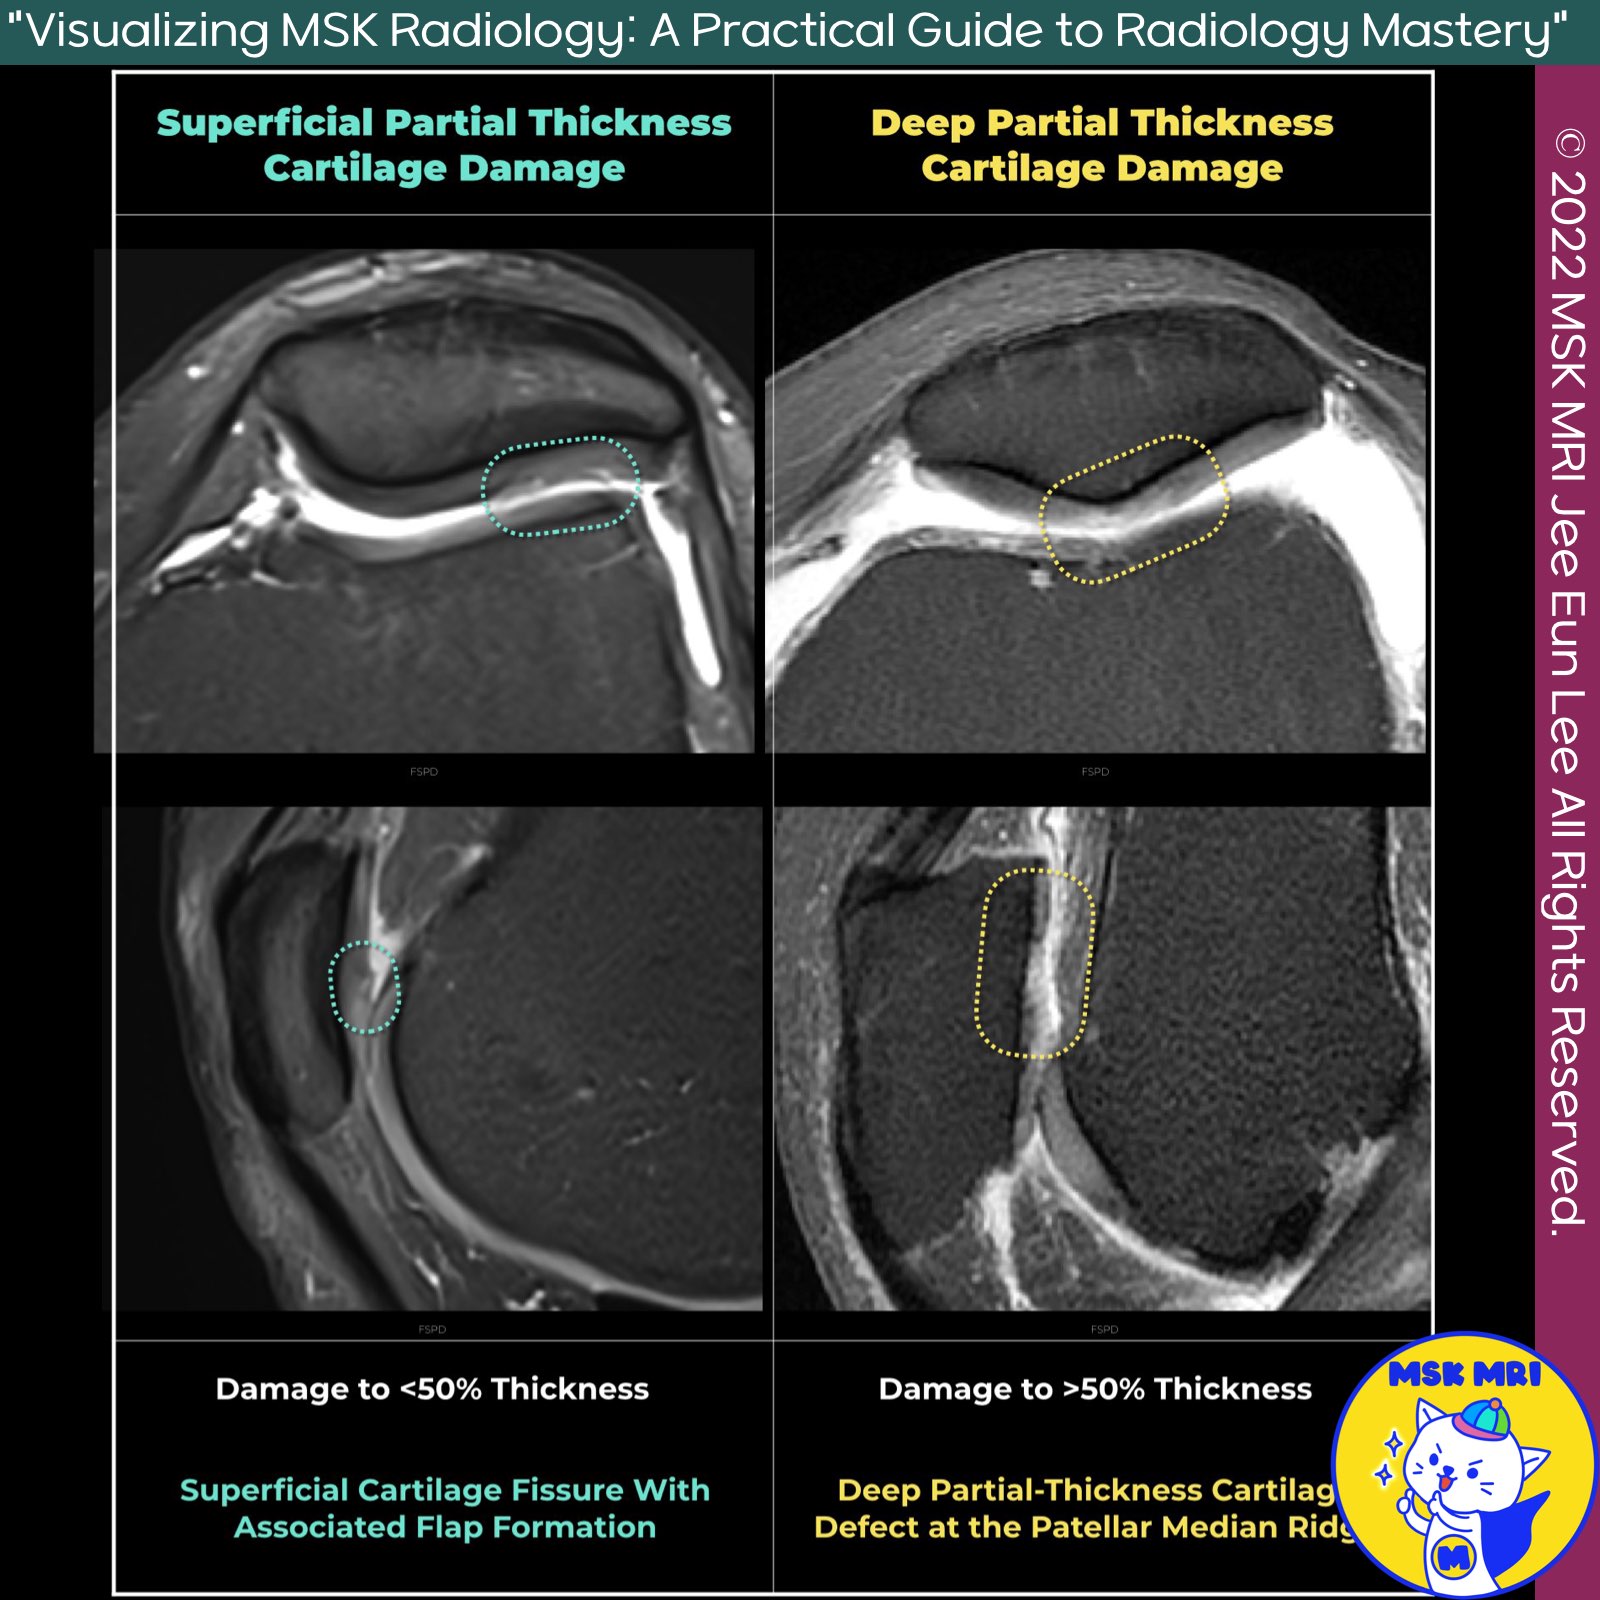

📌 Partial Thickness Cartilage Damage

- Modern surgical and MRI grading systems classify cartilage damage into four categories, ranging from cartilage softening to full-thickness damage.

✅ Grading Categories

- Category 1: Cartilage Softening

- Category 2: Damage < 50% Thickness

- Category 3: Damage > 50% Thickness

- Category 4: Full-Thickness Damage

✅ MRI Classification by ICRS

- The International Cartilage Repair Society (ICRS) classification system is widely accepted for MR imaging of articular cartilage lesions.

★ ICRS Grades

- Grade 2

- Lesions < 50% cartilage thickness

- Grade 3

- Lesions > 50% but not through the subchondral bone

- Includes chondral blisters, delamination, and chondral flaps

★ Grade 3 Subcategories

- Grade 3A

- Defect > 50% but not down to the calcified layer

- Grade 3B

- Defect > 50% down to the calcified layer

- Grade 3C

- Defect down to but not through the subchondral bone plate

- Grade 3D

- Defect > 50% with blisters

★ Imaging Limitations

Due to spatial resolution limitations, current MR imaging may not reliably distinguish between Grade 3a, 3b, and 3c.